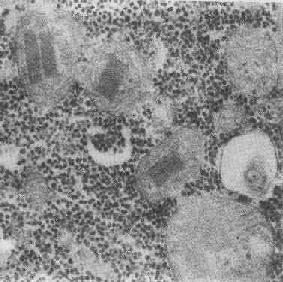

2.大小改变 细胞损伤时最常见的改变为线粒体肿大。根据线粒体的受累部位可分为基质型肿胀和嵴型肿胀二种类型,而以前者为常见。基质型肿胀时线粒体变大变圆,基质变浅、嵴变短变少甚至消失(图1-9)。在极度肿胀时,线粒体可转化为小空泡状结构(图1-10,图1-11)。此型肿胀为细胞水肿的部分改变。光学显微镜下所谓的浊肿细胞中所见的细颗粒即肿大的线粒体。嵴型肿较少见,此时的肿胀局限于嵴内隙,使扁平的嵴变成烧瓶状乃至空泡状,而基质则更显得致密。嵴型肿胀一般为可复性,但当膜的损伤加重时,可经过混合型而过渡为基质型。

图1-11 线粒体肿胀(基质型)空泡变(心肌缺氧)

线粒体为对损伤极为敏感的细胞器,其肿胀可由多种损伤因子引起,其中最常见的为缺氧;此外,微生物毒素、各种毒物、射线以及渗透压改变等亦可引起。但轻度肿大有时可能为其功能升高的表现,较明显的肿胀则恒为细胞受损的表现。但只要损伤不过重、损伤因子的作用不过长,肿胀仍可恢复。